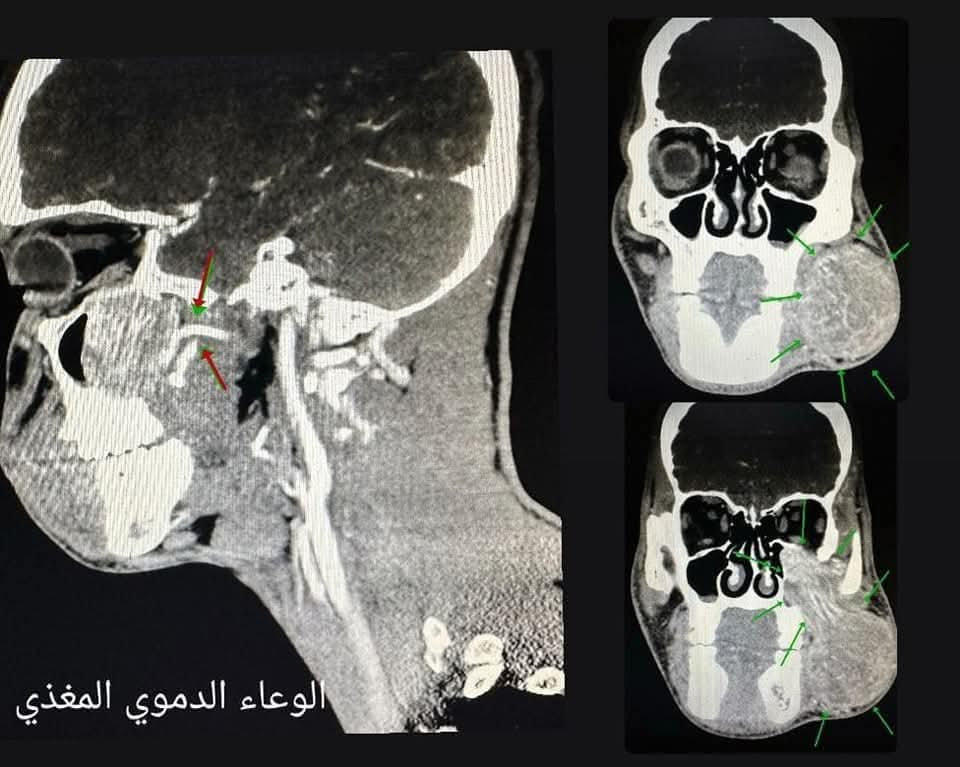

راجع مستشفى الحسين السلط الجديد أحد المواطنين لعيادة جراحة الوجه و الفكين وكان يشكو من انتفاخ متزايد في منطقة الخد وبعد اجراء الفحوصات الشعاعية و النسيجية ، تم تشخيص المريض بورم دموي حميد نادر، يسمى(juvenile nasopharyngeal angiofibroma)عادة ما ينبع في البلعوم الانفي ، الا انه في هذه الحالة نابع من منطقة الحفرة تحت الصدغية في قاع الجمجمة (infratemporal fossa)، ممتد الى الخارج بجانب الفك السفلي الى منطقة الخد. و بناءً على صور الاشعه، تم بفضل الله و كرمه عمل اجراء جراحي نوعي و معقد استمر لمدة ٨ ساعات و نصف، تم خلاله استئصال كامل للورم مع المحافظة الكاملة على الشرايين و الاعصاب الخامس و السابع ، و اغلاق الشريان المغذي للورم، دون حدوث أية مضاعفات تذكر، حيث تماثل المريض للشفاء و غادر غرفة العناية المشددة بصحة ممتازة. و تعتبر هذه العملية من العمليات المعقدة جدا و الخطيرة بسبب موقع الورم في قاع الجمجمة و ما يحيط به من اعصاب و شرايين و امتداده ال منطقة الخد جعله اكثر تعقيدا من ناحية جراحية. هذا ويحرص مستشفى الحسين السلط الجديد على توفير بيئة مناسبه و داعمة لعلاج الحالات الصحية المتقدمة و تلقي اعلى مستوى من الرعاية الصحية للمواطنين في محافظة البلقاء خصوصا و المملكة عموما.